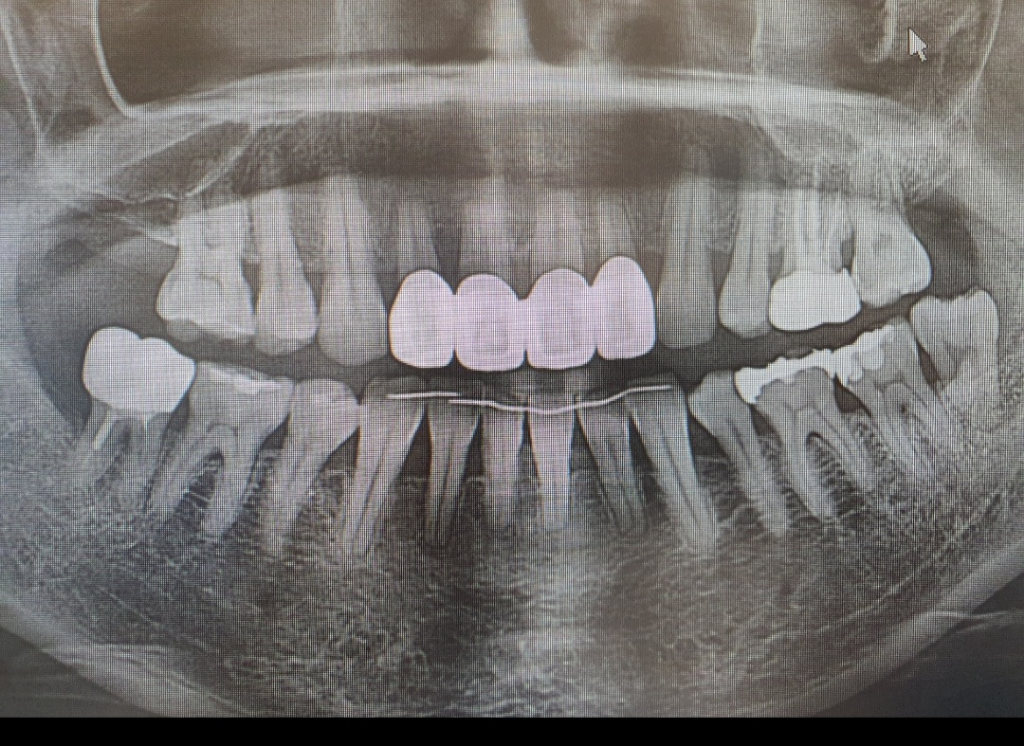

치근단 사진은 7월 7일에 찍은겁니다.

그리고 파노라마는 7월 5일에 찍었습니다.